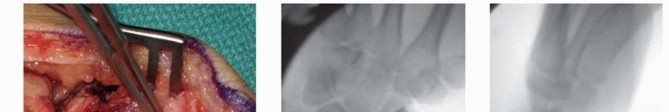

Correction of the humpback deformity is the most crucial biomechanical step. Two 0.045-inch Kirschner wires (K-wires) are inserted as joysticks: one into the distal scaphoid fragment and one into the proximal fragment. By applying an extension moment to the distal joystick and a flexion moment to the proximal joystick, the scaphoid is hinged open volarly. This maneuver restores the anatomical length of the scaphoid, corrects the lateral intrascaphoid angle, and simultaneously realigns the lunate out of its DISI posture. The resulting trapezoidal void on the volar aspect of the scaphoid is then precisely measured using a sterile caliper to determine the exact dimensions required for the bone graft.

Image

Attention is then turned to the distal radius for graft harvest. Through the proximal extent of our existing incision, the pronator quadratus is elevated off the volar aspect of the distal radius. A cortical window is mapped out based on the caliper measurements. Using an oscillating saw and fine osteotomes, a corticocancellous wedge is carefully harvested. The surgeon must ensure the structural integrity of the cortical face of the graft while capturing a robust volume of underlying cancellous bone.